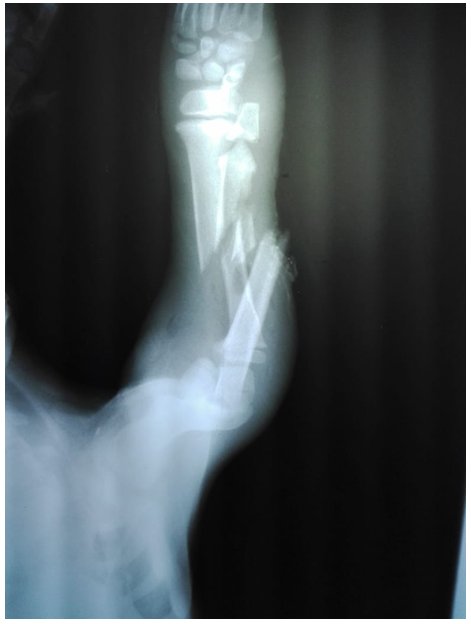

Como planes de diagnóstico se sugirieron, cuadro hemático y bioquímica sanguínea, en los resultados se observa que está dentro de los parámetros normales (tabla 1 y 2), y una radiografía en posición lateral y dorso ventral del antebrazo para observar radio y cubito parte distal, las imágenes radiográficas nos indica que es una fractura completa en bisel corto de radio en la diáfisis medial y fractura de cubito completa transversa a nivel diáfisis distal se observa en la (figura 1 y 2), las imágenes radiológicas de la fractura descrita, según la clasificación AO (Asociación para el Estudio de la Osteosíntesis) es de tipo 22-A3.

Figura 1 Radiografía vista lateral de radio cubito del lado derecho

Figura 2 Radiografía vista dorso ventral de radio cubito del lado derecho